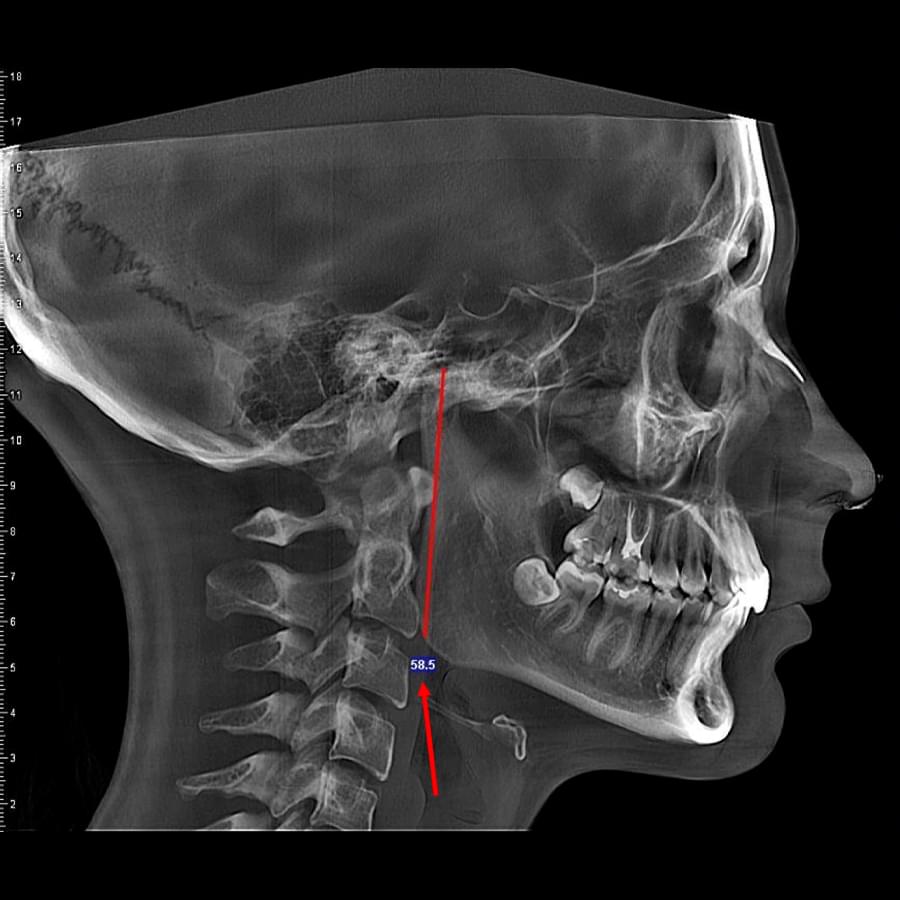

3D цефалометричний аналіз є сучасною технологією, яка дозволяє отримувати точніші,

комплексніші та надійніші дані про зубну та скелетну структуру. Ця технологія може стати

великим кроком в перед для ортодонтів, які хочуть забезпечити найкраще можливе лікування

своїх пацієнтів.

Успішна імплантація починається з бездоганної діагностики. Томограф PLANMECA забезпечує

зображення в реальному масштабі 1:1 без геометричних спотворень, що критично важливо для

вибору розміру та позиції імплантату.